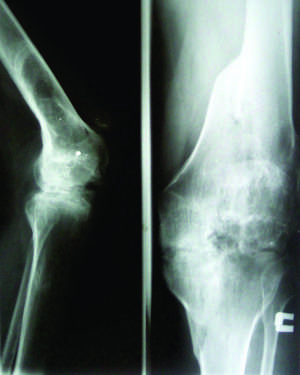

Հիվանդ՝ Ն.Մ., ծնված 1982 թվականին: 2007 թ. հոկտեմբերի 31-ին ԼՂՀ-ի սահմանին մարտական ծառայություն իրականացնելիս աջ ծնկահոդի շրջանում ստացել է հրազենային վիրավորում՝ 5.45 տրամաչափի երկու գնդակից: Առաջին գնդակը ծակել է ազդրի ս/3-ի կողմնային մակերեսով, անցել է ազդրի դիստալ էպիֆիզի միջով և առաջացրել միջային կոճի ներհոդային կոտրվածք, այնուհետև դուրս է եկել ծնկահոդի առաջա-դրսային մակերեսով: Երկրորդ գնդակը ծակել է ծնկահոդի կողմնային հոդաճեղքից 3 սմ. վերև՝ անցել ազդրի դիստալ մետաէպիֆիզով և դուրս է եկել ծնկահոդի առաջա-միջային մակերեսով (նկար 1):

Վնասվածքները ստանալուց հետո տեղափոխվել է Ստեփանակերտի զինվորական հոսպիտալ: Այնտեղ ախտորոշվել է աջ ծնկահոդի հրազենային, թափանցող վիրավորում, բազմաբեկոր կոտրվածք: Այնուհետև բուժումը 3 ամիս տևողությամբ շարունակվել է Ստեփանակերտի վերականգնողական կենտրոնում՝ աջ ծնկահոդում 30 աստիճան:

Հիվանդը 2009 թվականի ապրիլի 4-ին դիմեց ԵՊԲՀ-ի վնասվածքաբանության և օրթոպեդիայի կլինիկա՝ հետագա բուժման նպատակով:

Զննման ժամանակ հիվանդը քայլում էր ինքնուրույն՝ կաղալով աջ ոտքի վրա, երկու կոնտուրները հարթված էին, նկատվում էր հոդի միջային մակերեսից չափերի մեծացում:

Հիվանդի մոտ առկա էր աջ ստորին վերջույթի թվացյալ կարճացում մոտ 7 սմ., աջ ծնկահոդը ծալված էր մոտ 35-40 աստիճան, աջ ծնկահոդում ակտիվ շարժումները բացակայում էին, պասիվ շարժումների ժամանակ նկատվում էր զսպանակաձև դիմադրություն, աջ կոնքազդրային և սրունքթաթային հոդերում շարժումներն ամբողջ ծավալով ազատ, անցավ էին: Վիզուալ աջ ծնկահոդի դրսային-վերին մակերեսին նկատվում էին մոտավորապես 1,5 սմ. տրամաչափի երկու հետվնասվածքային սպիներ, աջ ծնկահոդի առաջային մակերեսին՝ հոդաճեղքի մակարդակում, նկատվում էր մոտ 7-8 սմ. երկարությամբ և 2 սմ. լայնությամբ հետվնասվածքային սպի՝ շոշափելիս անցավ: Պուլսը և զգայունությունը պերիֆերիայում պահպանված էր: